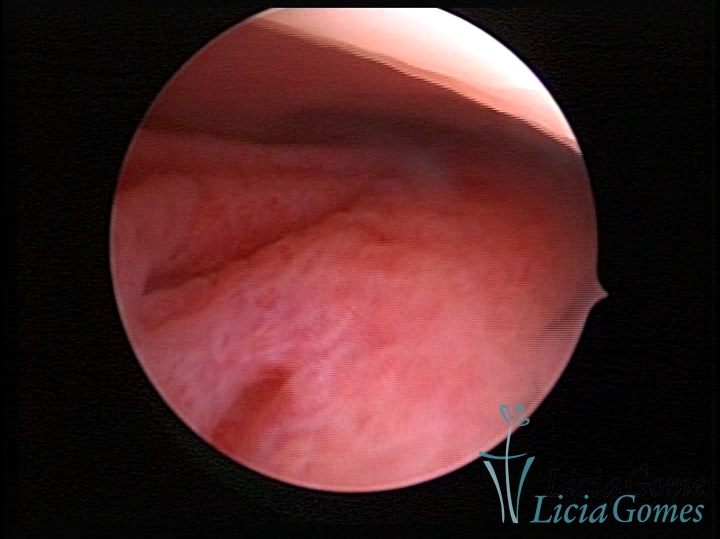

ENDOCERVICAL POLYPS

Benign tumors resulting from the reactive focal proliferation to inflammatory processes or hyperestrogenism situations, which may be sessile (with a large implantation) or stalked.